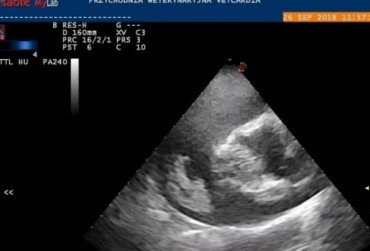

Metody małoinwazyjne w kardiologii weterynaryjnej. Czy chirurg jest jeszcze potrzebny? Opis przypadku

Artykuł przedstawia różne metody usunięcia worka osierdziowego. Prezentuje zarówno metody klasyczne, jak i małoinwazyjne, pokazując zalety i wady każdej z nich. Dzięki przedstawionemu opisowi przypadku pozwala zrozumieć, czym należy się kierować przy wyborze odpowiedniej metody operacji.